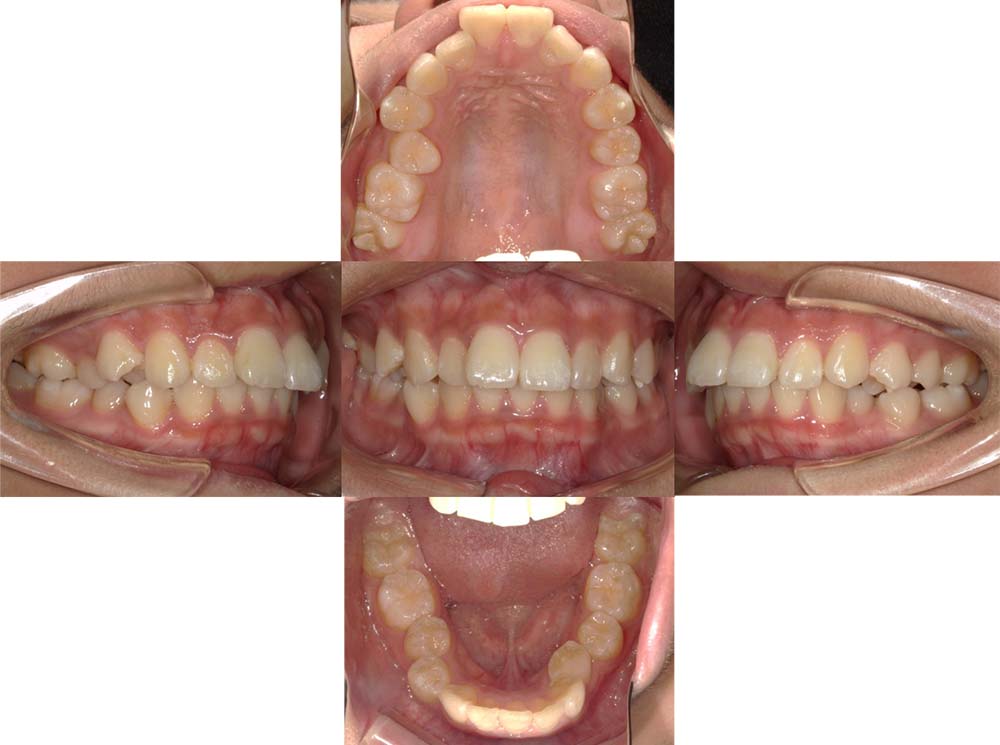

症例02

| 主訴 | 下あご顎が出ている。曲がっている。 |

| 診断名あるいは主な症状 | 反対咬合、非対称、空隙歯列、過蓋咬合 |

| 年齢/性別 | 19歳・女性 |

| 矯正ステージ | 大人の矯正治療 |

| 治療方法 | ワイヤー矯正、顎矯正手術の施行 |

| 抜歯部位/抜歯有無 | 非抜歯 |

| 治療内容 | 上下顎歯列を並べた後に顎矯正手術の施行。 |

| 費用 | 保険治療 |

| 治療期間 | 3年2ヶ月 |

| 主なリスク・副作用 | 痛み、歯根吸収、歯肉退縮、虫歯、後戻り |